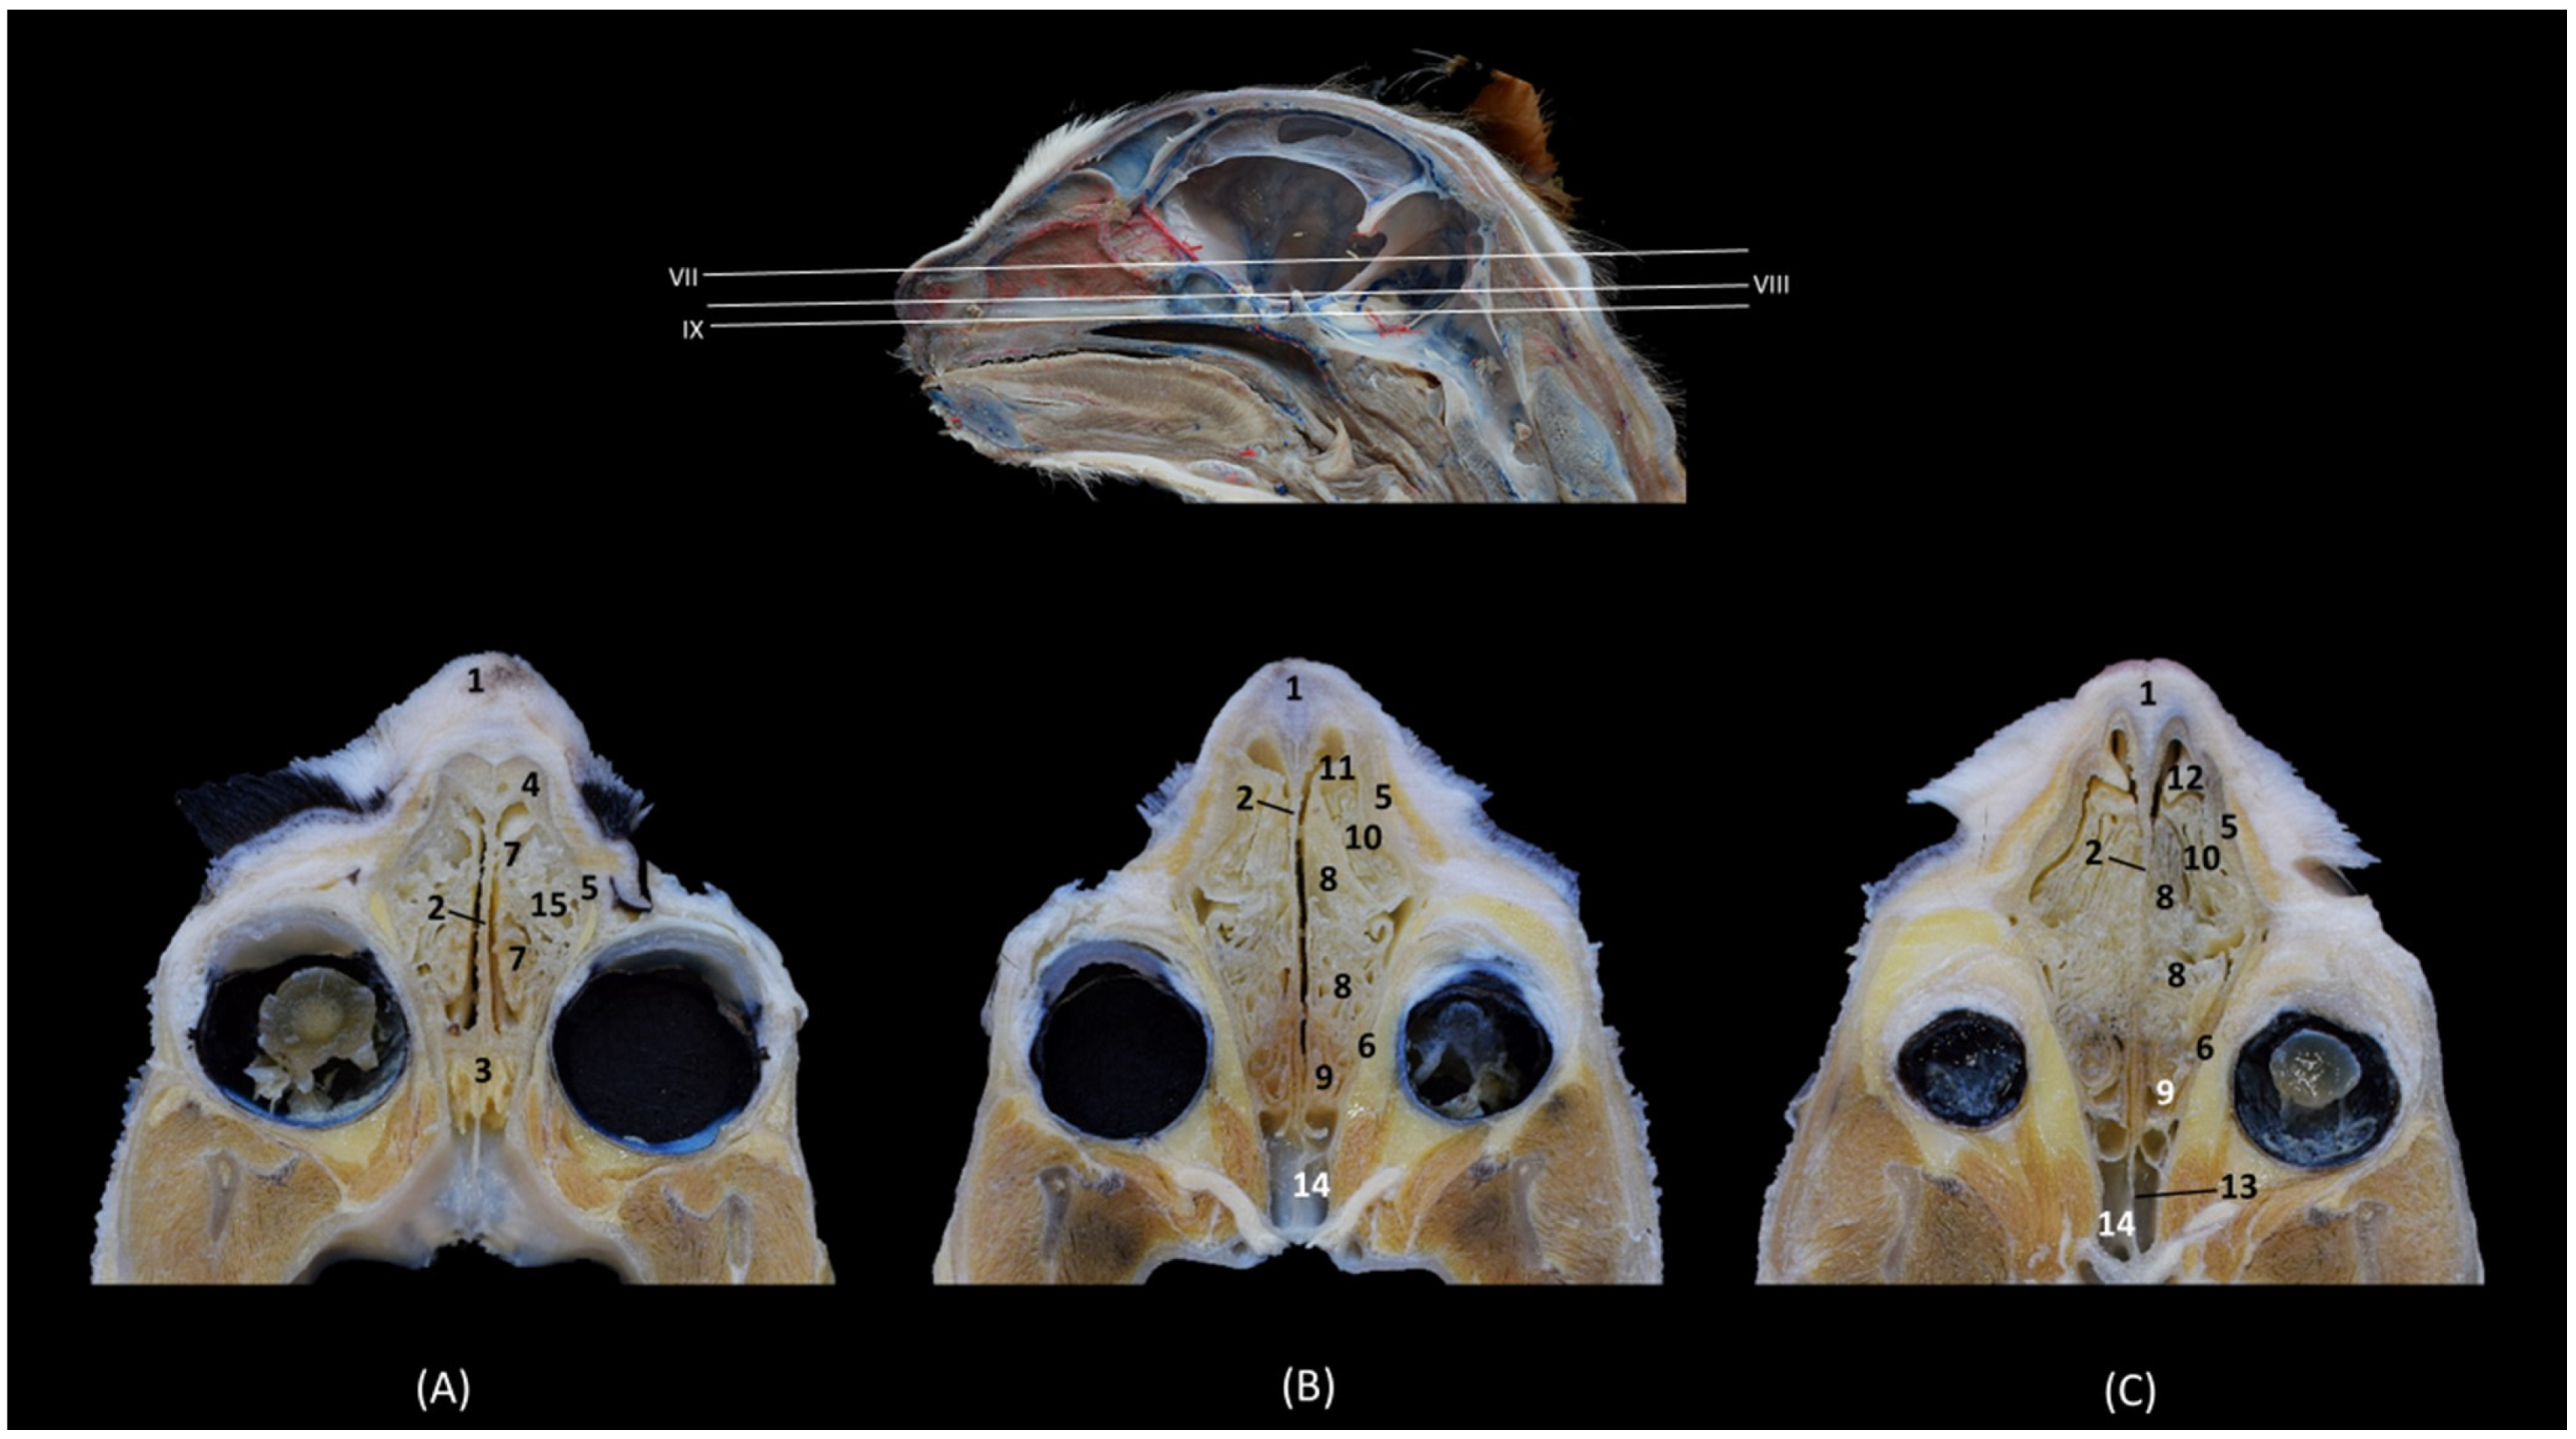

In the following transverse section (Figure 6), in the medial part of the nasal cavity, the ventral nasal concha was already decreasing in size while the third endoturbinate reaches its greatest development. At this level, the dorsal nasal concha also increases in size. Furthermore, the three ectoturbinates could be clearly identified. From dorsal to ventral, the first, the third and the second ectoturbinates were observed.

Figure 6. Transverse anatomical sections of the cat’s head at the level of the middle part of the nasal cavity; respiratory part. (A): Rostral view, level section V. (B): Caudal view, level section VI. 1. Frontal bone; 2. Frontal sinus: septum; 3. Nasal septum: cartilage; 4. Vomer; 5. Maxilla: palatine process; 6. 1st premolar tooth: root; 7. Frontal bone: orbital surface; 8. 1st ectoturbinate; 9. 2nd ectoturbinate; 10. 3rd ectoturbinate; 11. Dorsal nasal concha; 12. Middle nasal concha; 13. 3rd endoturbinate; 14. Ventral nasal concha; 15. Conchal crest of the maxilla; 16. Maxillary recess; 17. Vomeronasal organ; 18. Nasal cavernous plexuses; 19. Frontal sinus.

In the next transverse section (Figure 7), the end of the ventral nasal concha was seen. At this level a lateral attachment of the third endoturbinate to the frontal bone could also be identified. Ectoturbinates also decrease at this level and the greater size of the frontal sinus was observed. At this stage, the vomeronasal organ reaches its caudal extent.

Figure 7. Transverse anatomical sections of the cat’s head at the level of the caudal part of the nasal cavity; respiratory part. (A): Rostral view, level section VII. (B): Caudal view, level section VIII. 1. Frontal bone; 2. Frontal sinus: septum; 3. Nasal septum: cartilage; 4. Vomer; 5. Maxilla: palatine process; 6. 2nd premolar tooth: root; 7. Frontal bone: orbital surface; 8. 1st ectoturbinate; 9. 2nd ectoturbinate; 10. 3rd ectoturbinate; 11. Dorsal nasal concha; 12. Middle nasal concha; 13. Conchal crest of the 3rd endoturbinate; 14. 3rd endoturbinate; 15. Conchal crest of the maxilla; 16. Ventral nasal concha; 17. Maxillary recess; 18. Frontal sinus; 19. Vomeronasal organ; 20. Nasal cavernous plexuses.